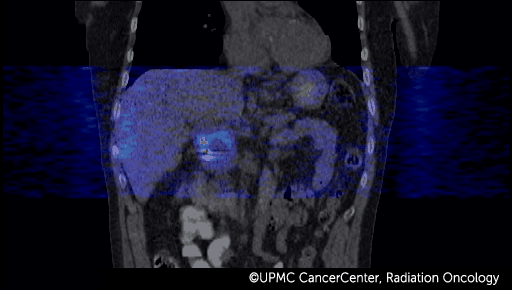

4D PET-CT combines positron emission tomography (PET) with computed tomography (CT) to take advantage of these faster, more accurate technologies.

- Captures the movement of your organs and tumor over time, while also recording the metabolism of the tumor.

- Creates the most complete and accurate imaging data on your tumor and critical organs.

- Allows your oncologist to see how your tumor moves with breathing and other normal body motions.

4D PET and 4D CT images fuse together and show:

- How your tumor moves.

- How your breathing affects the tumor.

- How movement of nearby organs affects the tumor.